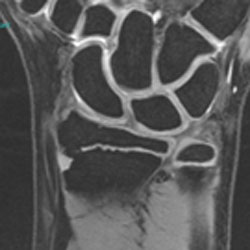

Traumatic Physeal Arrests at the Wrist

Current Concept Review

Laura Bellaire, Carley Vuillermin, Suzanne Steinman, Walter Truong, Donald Bae, Doug Wallace, Christine Ho